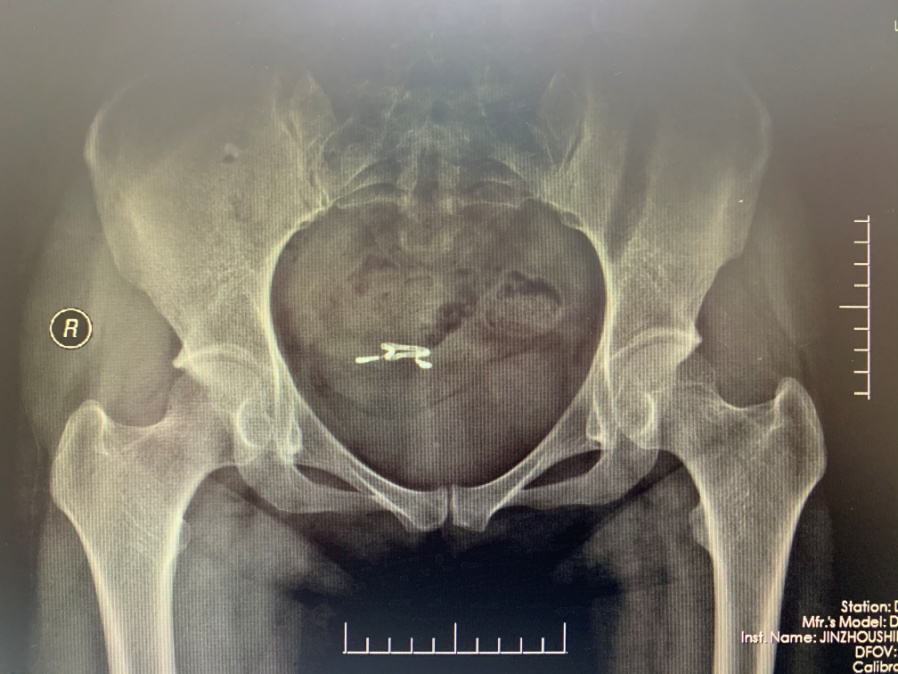

08-042023随着现代医疗技术的发展,学科的分类越来越细化,专业之间的壁垒逐渐加深。为了弥补这一缺陷,越来越多的医院开设了多学科诊疗的模式,简称MDT,全方位为患者提供医疗服务。 为了更好...